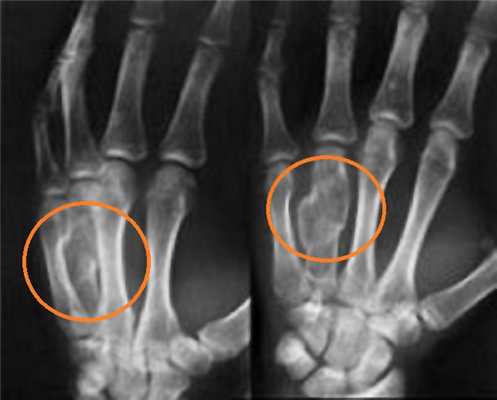

Клинические проявления у пациента: боль и ограничение движений после падения на вытянутую руку 4 месяца назад.

Перелом ладьевидной кости с явлениями асептического некроза проксимального полюса и, связанного с ним, остеоартрита. Ладьевидный перелом обычно происходит из-за падения на вытянутую руку, которое приводит к гиперэкстензии лучезапястного сустава.

Аваскулярный (асептический) некроз нередко сопутствует переломам проксимальной части ладьевидной и переломам полулунной кости, а также неадекватно репонированным и иммобилизированным переломам этих костей. Основная причина - нарушение трофики участка кости при повреждении питающих артерий.